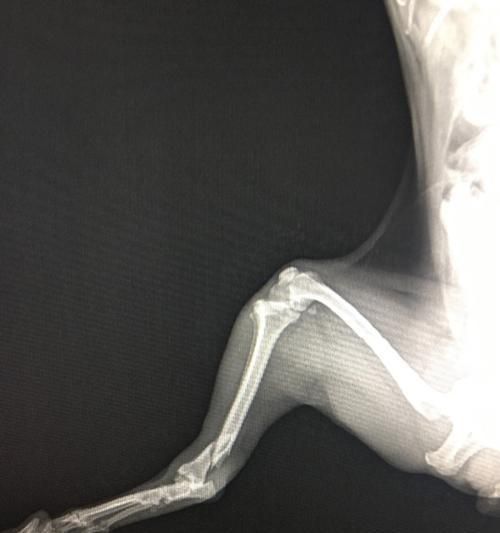

四、常见的狗狗腿骨折类型介绍

狗狗的腿骨折有不同的类型,包括完全性骨折、部分性骨折和开放性骨折。了解这些类型对我们理解狗狗腿骨折的程度和处理方法非常重要。